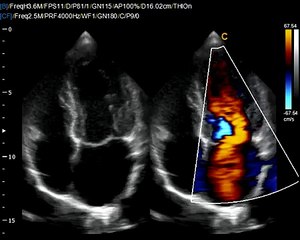

Chison Q9 Cardiac Sonography with phased array probe. The color doppler Q9 machine is affordable and masterfully designed. Can be used in all examinations.